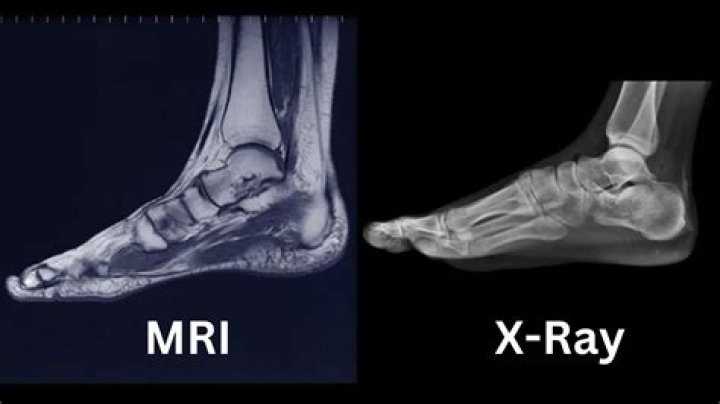

In the foot and ankle, MRI can be used to diagnosis the following conditions:Tendon injuries.Ligament injuries.Cartilage injuries.Fractures.Tumors (soft t...